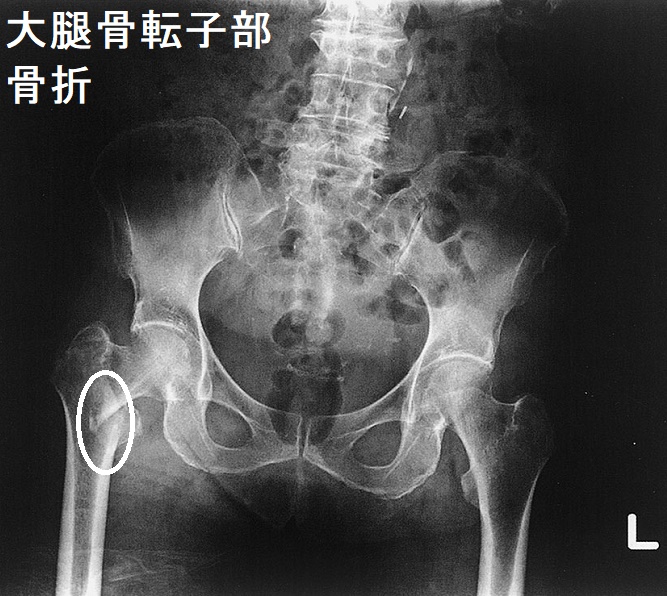

心房細動(Af)や狭心症から甲状腺機能亢進症/バセドウ病がみつかる場合もあります。[Nihon Ronen Igakkai Zasshi. 1996 Mar;33(3):191-5.] - 特に老年期女性は元々、閉経後骨粗鬆症があるため、さらに骨が悪くなる。[高齢者バセドウ病の大腿骨頚部骨折と大腿骨転子部骨折(脚の付け根の骨折)]

加齢による骨粗しょう症で、ただでさへ骨折しやすいのに、高齢の甲状腺機能亢進症/バセドウ病患者は、甲状腺ホルモンの作用で骨分解が加速され、輪をかけて骨折の危険が高くなります(甲状腺機能亢進症/バセドウ病の骨粗しょう症 )。

高齢者の大腿骨頚部骨折後に骨接合術をしなければ寝たきりになり、認知症・筋肉量減少によるサルコペニアが進行します。転倒しやすい生活環境を改善し、ヒッププロテクターを装着するのもよいでしょう。

また、骨接合術をしても高齢のため手術合併症も多く、